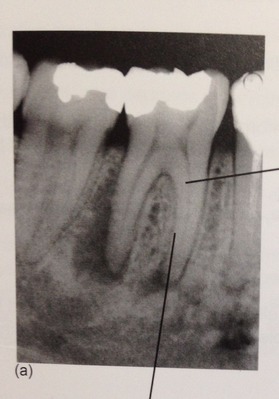

レントゲンで根の先が黒くなり、

膿んで骨がとけて、

ここに穴が開いてますね!

細菌が根の先にまで 進入してくると、

骨の細胞は細菌と戦えないんです。

一旦、骨がとけて肉芽って呼ぶ炎症性のお肉に変わります。

こんなに大きな穴でも、治ります。

少し根っ子を削るので、短くはなりますが。